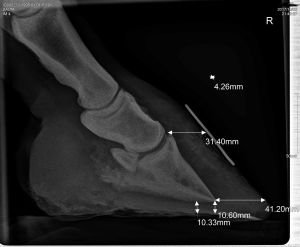

V tom momente ale náš príbeh začal paradoxne smerovať k lepšiemu. V jednom momente sa stretlo niekoľko priaznivých momentov. V stajni býva náš kamarát, ktorý je zhodou okolností kováč a kopytár. Salte sme okamžite nechali urobiť rentgeny, hoci s veľkou námahou pre jej bolesti a neschopnosť stáť. Blahorečila som výcviku pozitívnou motiváciou, ktorej sa venujem už niekoľko rokov a vďaka ktorej Salta bola ochotná spolupracovať iba za „kliknutie“ (odmenu dostať nemohla vzhľadom na prísnu diétu pri akútnom schvátení) aj za hranicou bolesti. Vďaka kováčovi snímky vyzerali tak, ako majú rentgenové snímky schváteného kopyta vyzerať, teda kopytnú stenu sme označili kovovými značkami, rovnako ako koniec strelu. Žiaľ, až na ojedinelé výnimky, snímky, ktoré vám urobí väčšina u nás dostupných veterinárov, nebudú dostatočne použiteľné, pretože kopytá nebudú správne označené. Takže súkromná rada z mojej strany: ak voláte veterinára rentgenovať kopytá s podozrením na schvátenie alebo už schvátené kopytá, pripravte si vopred lepiacu pásku, kus tenkého drôtu a pripináčik, vet ich pravdepodobne nebude mať 🙂

Na základe rtg snímkov urobil náš kopytár okamžite trim. Všetky zásahy na kopytách sme dokumentovali fotkami a posielali na konzultácie do skupiny dr. Kellon, o ktorej ešte bude reč. Kopytár sa Saltiných kopýt ujal s veľkým entuziazmom a trim jej od schvátenia robí každé dva týždne. Prvé dni prežila kobylka na polystyrénových papučiach, ktoré sa denne museli meniť, potom našťastie prišli špeciálne botky pre schvátené kone „Cloud“ od Easyboots. Sú fakt dobré a Salte hodne pomohli. Nerada na toto obdobie spomínam a dúfam, že nikdy nič podobné už nezažijem.